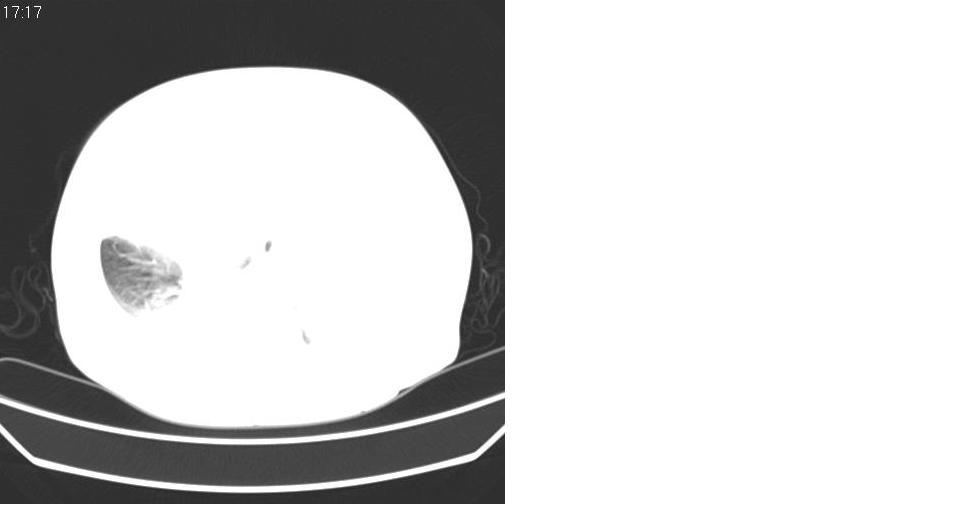

以下是引用liaizhi在2007-7-11 15:41:00的发言:[br]两肺纹理增粗,肺门影增大,气管支气管通畅。升主动脉壁及冠状动脉壁钙化。左房左室稍扩大。心包积液,胸腔积液。考虑冠心病并心功能不全,肺水肿,胸腔积液。

以下是引用zhangzhongshou在2007-7-11 13:16:00的发言:[br]1、冠状动脉钙化[br]2、心包积液[br]3、右侧胸腔积液[br]大家都考虑心衰,冠状动脉钙化、肺纹理增强,胸腔积液、心包积液,表面上是支持,但是为什么右侧有较多积液,左侧没有呢? 如果用结核性胸膜炎,并结核性心包炎也可解释,请楼主进一步提供临床资料。